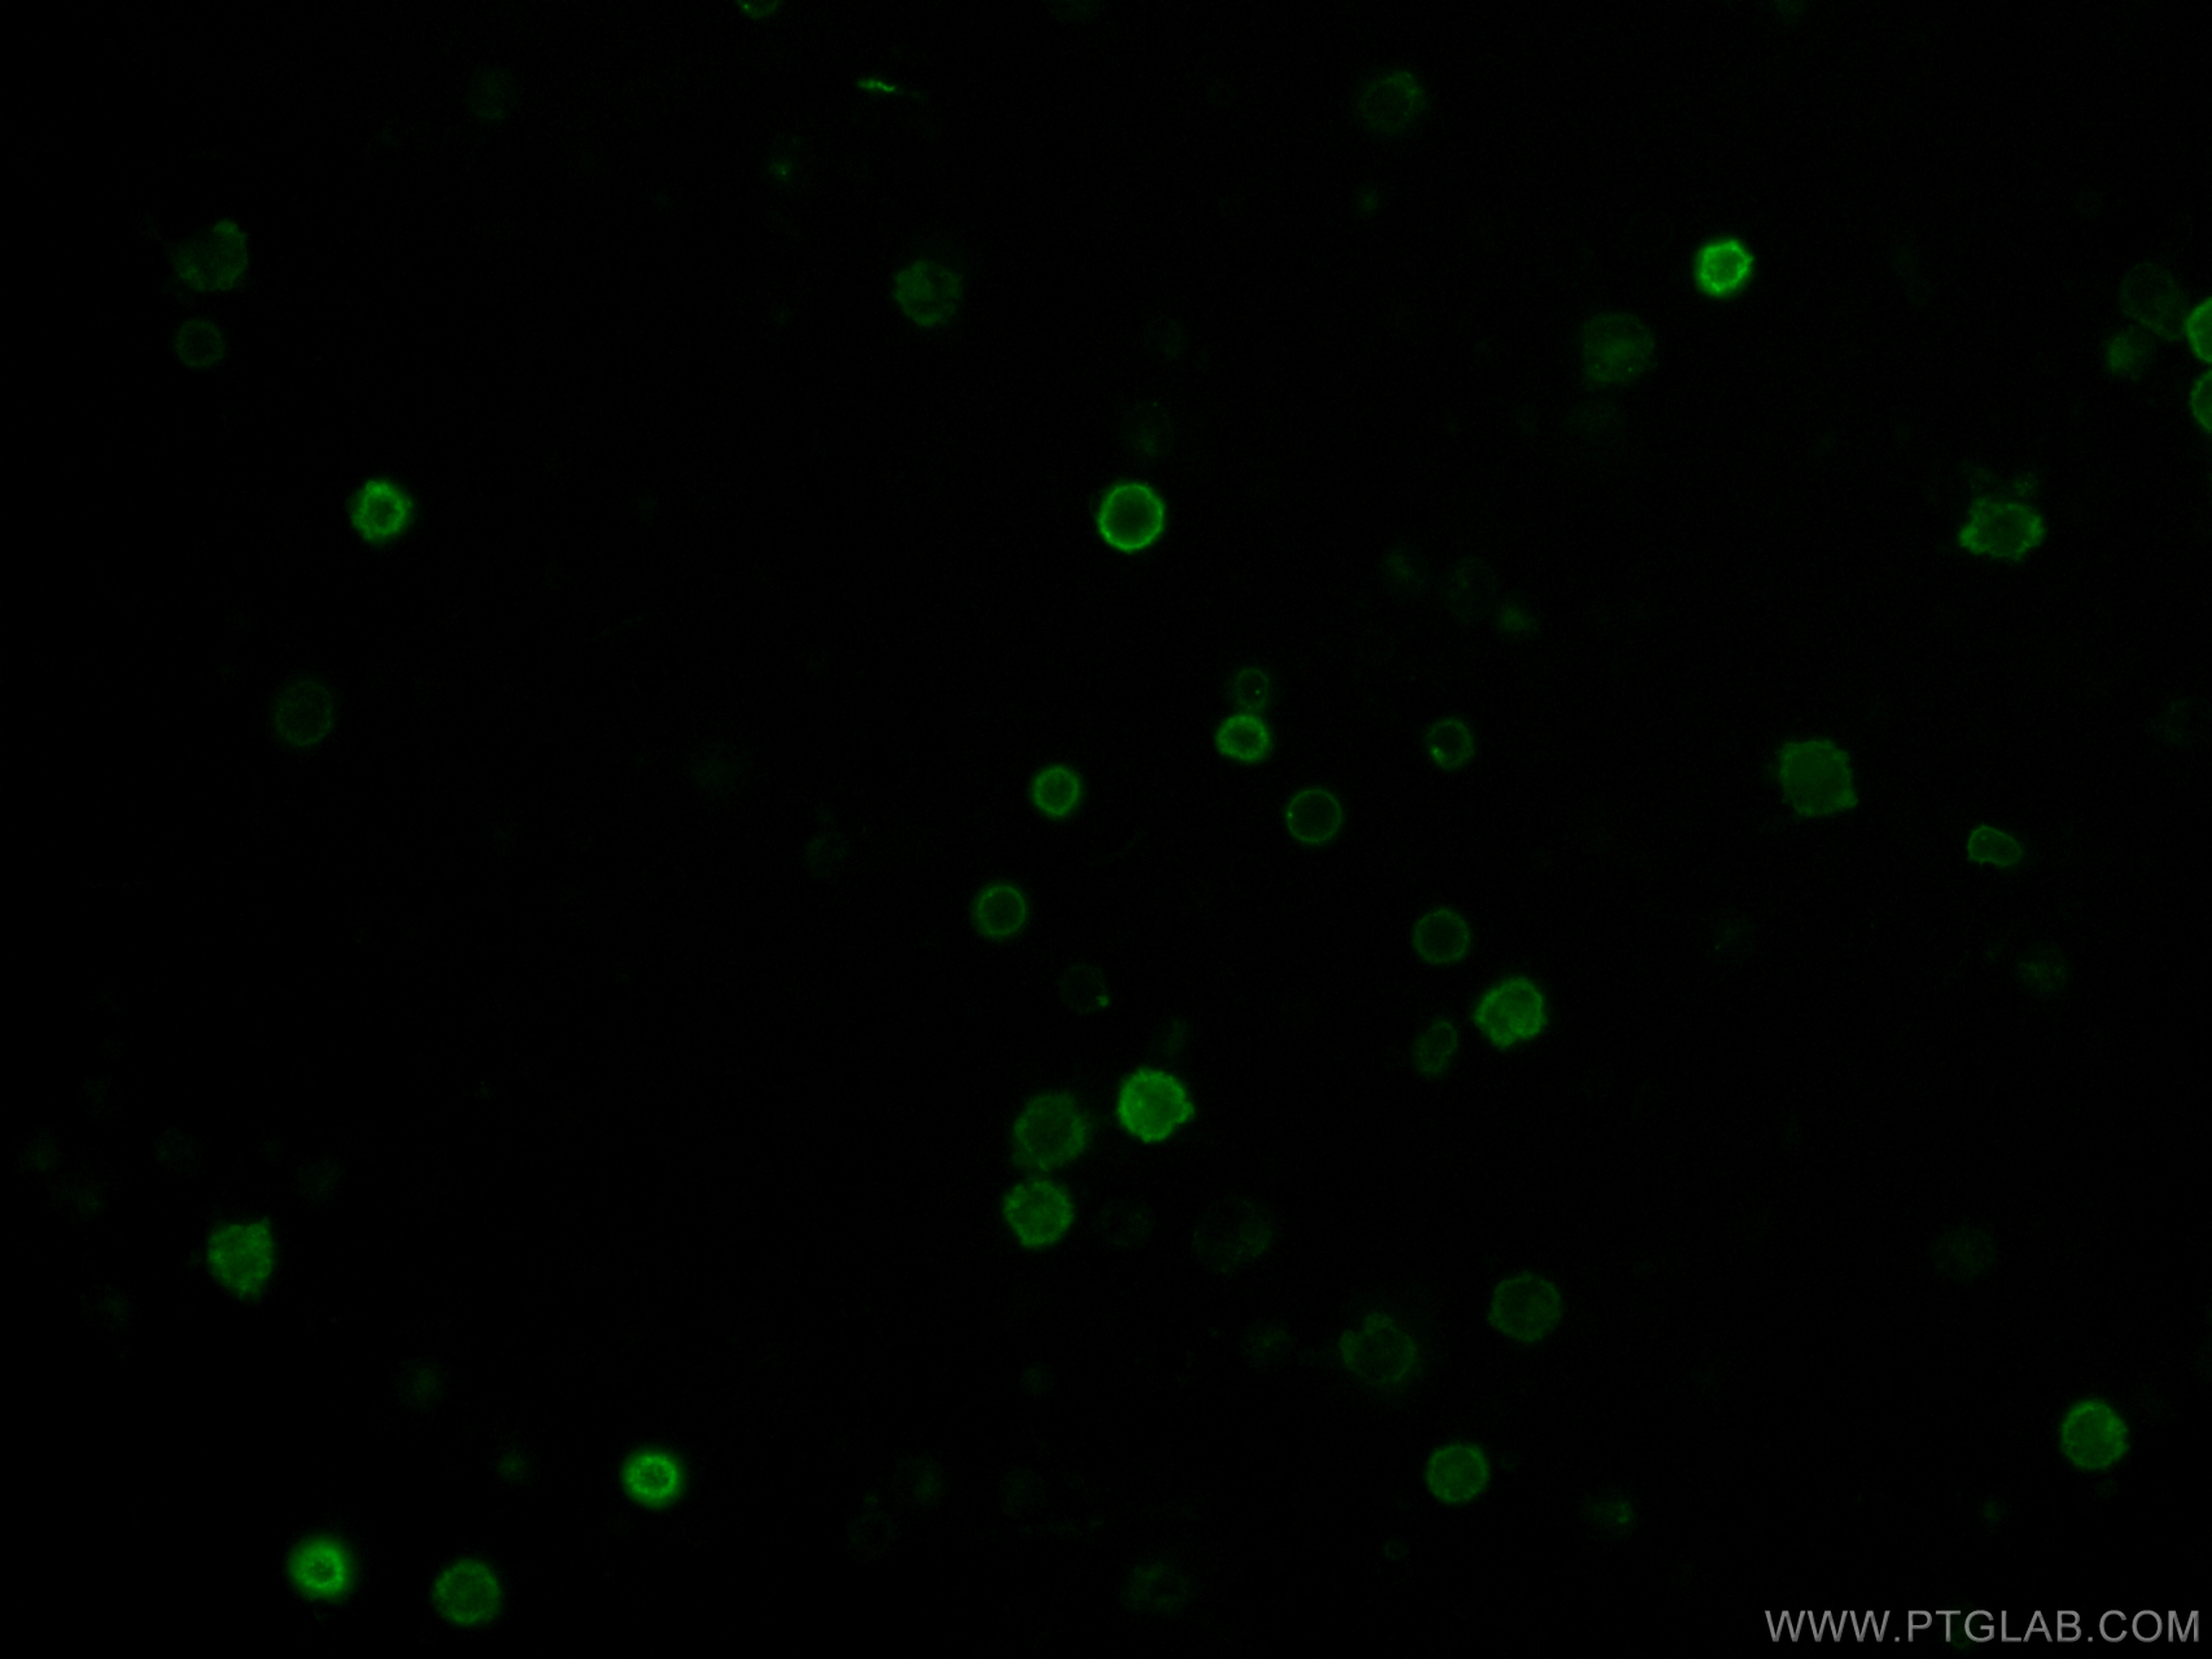

La protéine CD38 est une protéine de type cluster de différenciation, exprimé à la surface des cellules immunitaires. Elle est encodée par le gène CD38 situé sur le chromosome 4 humain.

Sous forme de monomère ou de dimère, elle interagit avec la protéine CD19.

Elle est exprimée à la surface de certaines cellules leucémiques de type myéloïde et sa stimulation participe à la prolifération de ces dernières.